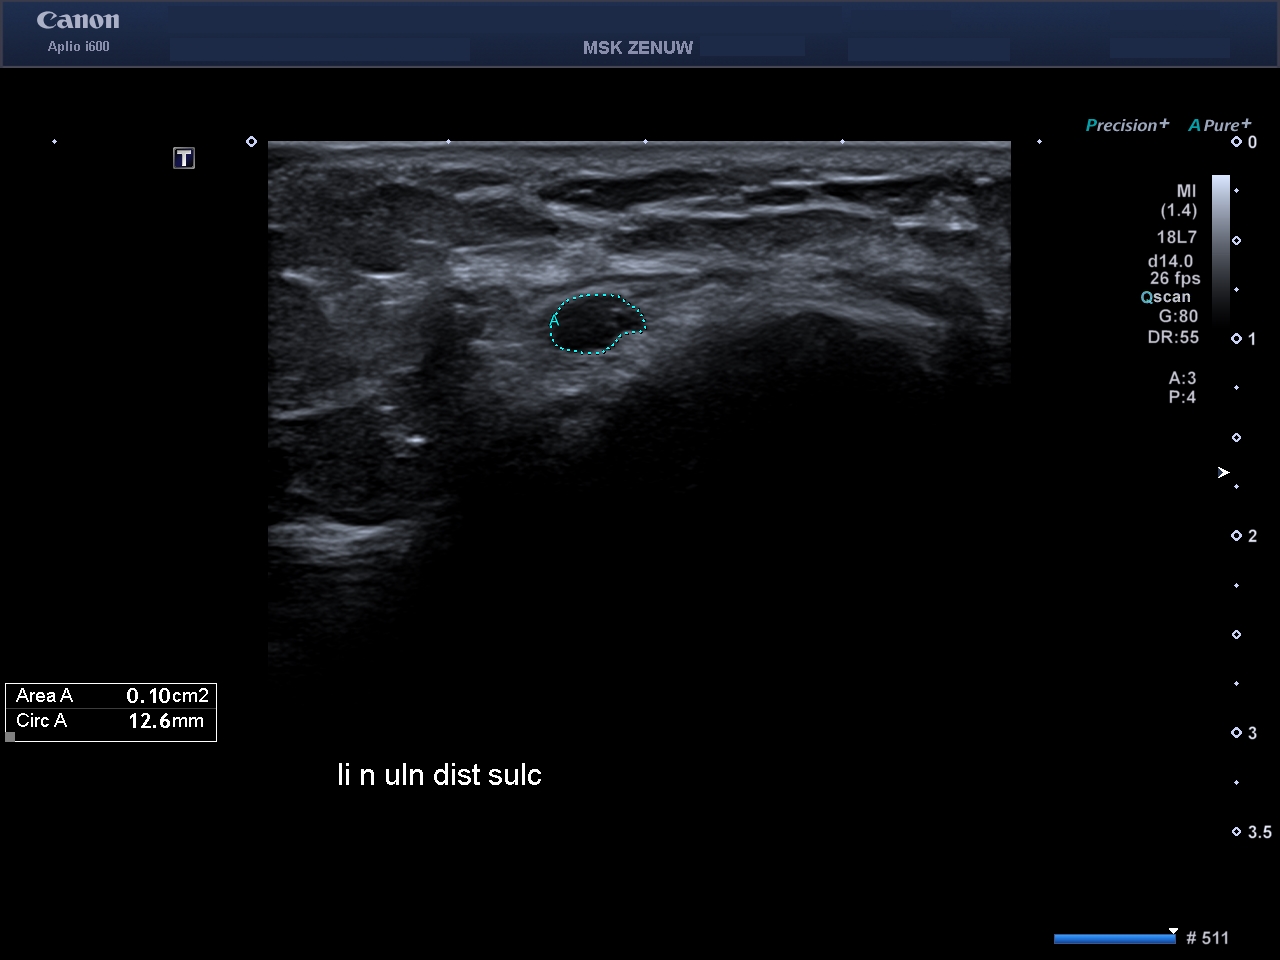

Представляємо вам клінічні випадки візуалізації періферійніх нервів на Aplio i800 з використанням високочастотного датчика 24 MHz. Ці приклади яскраво говорять самі за себе.